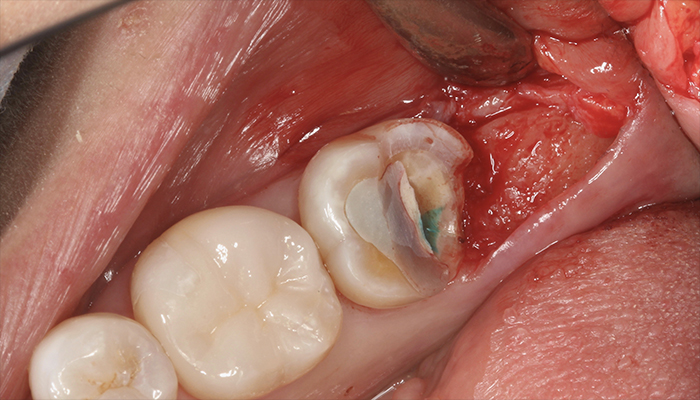

術中:フラップ翻転時

歯肉の盛り上がりに相当する部分に骨の隆起を認める。